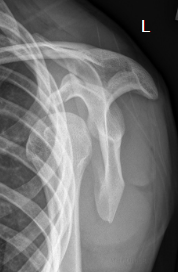

name the x-ray/position/method

transthoracic lateral shoulder (lawrence method)

evaluation criteria for transthoracic lateral shoulder (lawrence method)

Proximal ½ of humerus &

scapulohumeral joint

demonstrated without

superimposition of the

opposite shoulder

Overlying ribs & lung marking

blurred